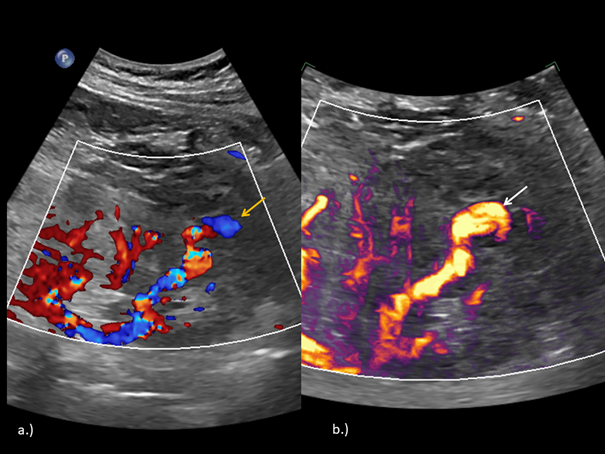

The Color Doppler and Micro-flow Imaging examinations depicted a ying-yang swirling motion blood flow within the lesion. Because an active bleeding could not be excluded by color Doppler, the examination was complemented with CEUS. (Figure 2)

Figure 2 Delimitation of the vascularized renal lesion (arrow) on color Doppler (a) and MFI (b).